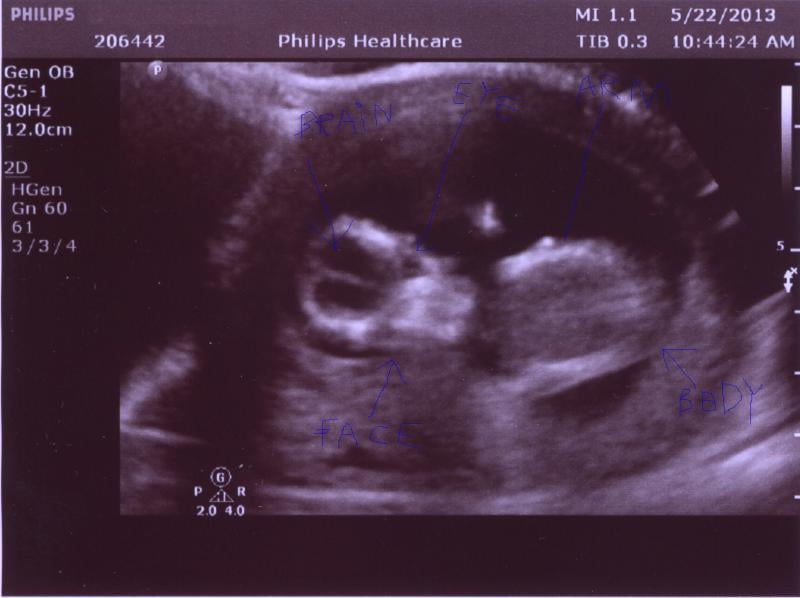

Below is a collection of prenatal ultrasound pictures from the Imaging Technology News (ITN) archive. Use the arrows to click through the image gallery. It includes transvaginal ultrasound images and fetal echocardiogram images. Fetal imaging is referred to by many names, including pregnancy sonograms, pregnancy ultrasound, endovaginal ultrasound, obstetric ultrasound, OB ultrasound, baby ultrasound, prenatal ultrasound. Fetal heart ultrasound is also called baby echo or prenatal echo.